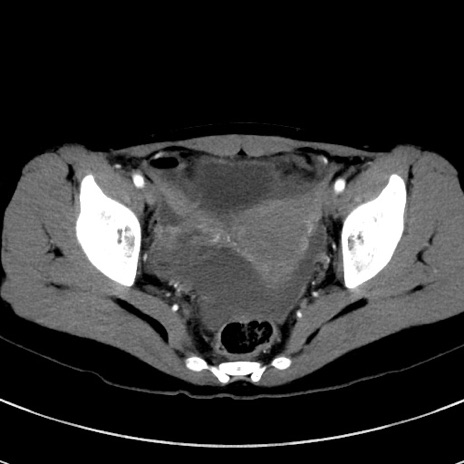

症例17(横断像)

【症例】20歳代女性

【主訴】嘔吐、下腹部痛

【現病歴】昨日夕食後に嘔吐し下腹部痛が出現。本日になっても嘔吐持続し改善しないため来院。

【身体所見】意識清明、BT 37.2℃、BP 108/67mmHg、腹部:平坦、やや硬、下腹部正中から右にかけて圧痛あり、反跳痛軽度あり、tapping pain(+)。

【データ】WBC 13600、CRP 14.94

冠状断像